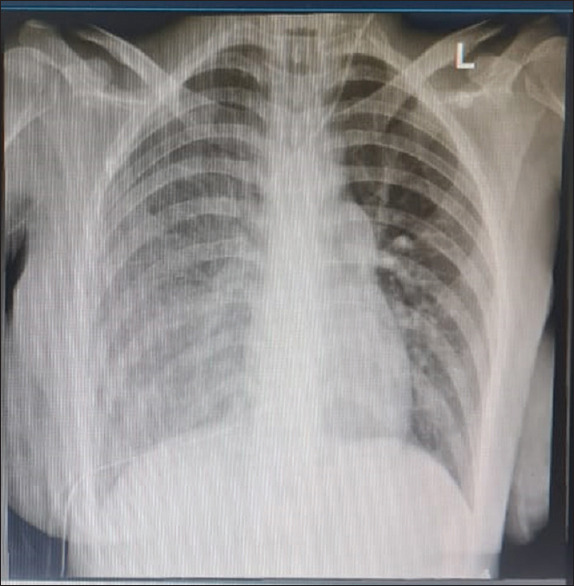

Abstract: Re-expansion pulmonary edema (RPE) is a rare complication of minimally invasive cardiac surgery (MICS). We present a case of RPE following atrial septal defect (ASD) closure using a thoracotomy approach and cardiopulmonary bypass (CPB). REP contributes to significant morbidity and extends the length of stays in the intensive care unit. Understanding the pathophysiology and risk factors of RPE allows us to prevent or minimize the incidence.

Abstract Image